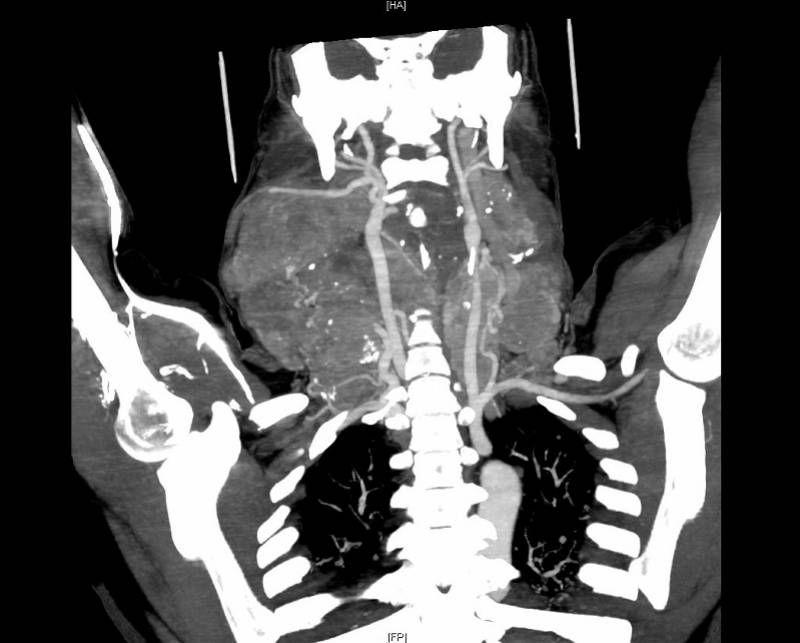

入院后经过超声及CT检查 , 黄晓明教授团队发现何女士的巨大甲状腺肿物已向下进入胸骨后方 , 压迫气管 , 并将喉推向一侧 。 甲状腺细针穿刺病理检查提示 , 甲状腺乳头状癌伴颈部淋巴结转移 , 最大直径超过20厘米 , 部分肿物已经探及颈后区和锁骨下方 。 术前胸部CT提示双肺多发转移瘤 。

术前CT片显示颈部巨大甲状腺癌及淋巴结转移瘤 , 包绕颈部大动脉